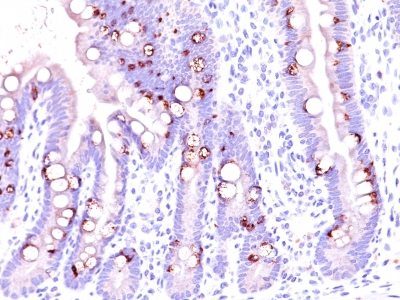

识别 520 kDa 的单一糖蛋白,确定为粘蛋白 2 (MUC2)。该 MAb 未显示与人乳脂肪球膜、MUC1 或 MUC3 发生交叉反应。其表位被定义为 GTQTP (GlyThrGlnThrPro)。粘蛋白是高分子量糖蛋白,构成保护胃上皮的粘液层的主要成分。MUC2 在小肠和结肠的杯状细胞中特异性表达;在大约 65% 的结肠癌和大约 40% 的胃癌中。MUC2 很少在胃肠道外表达,但乳腺癌粘液癌和卵巢透明细胞癌除外。

胃肠 (2002) 123(4):1052-1060。(IHC, FFPE)